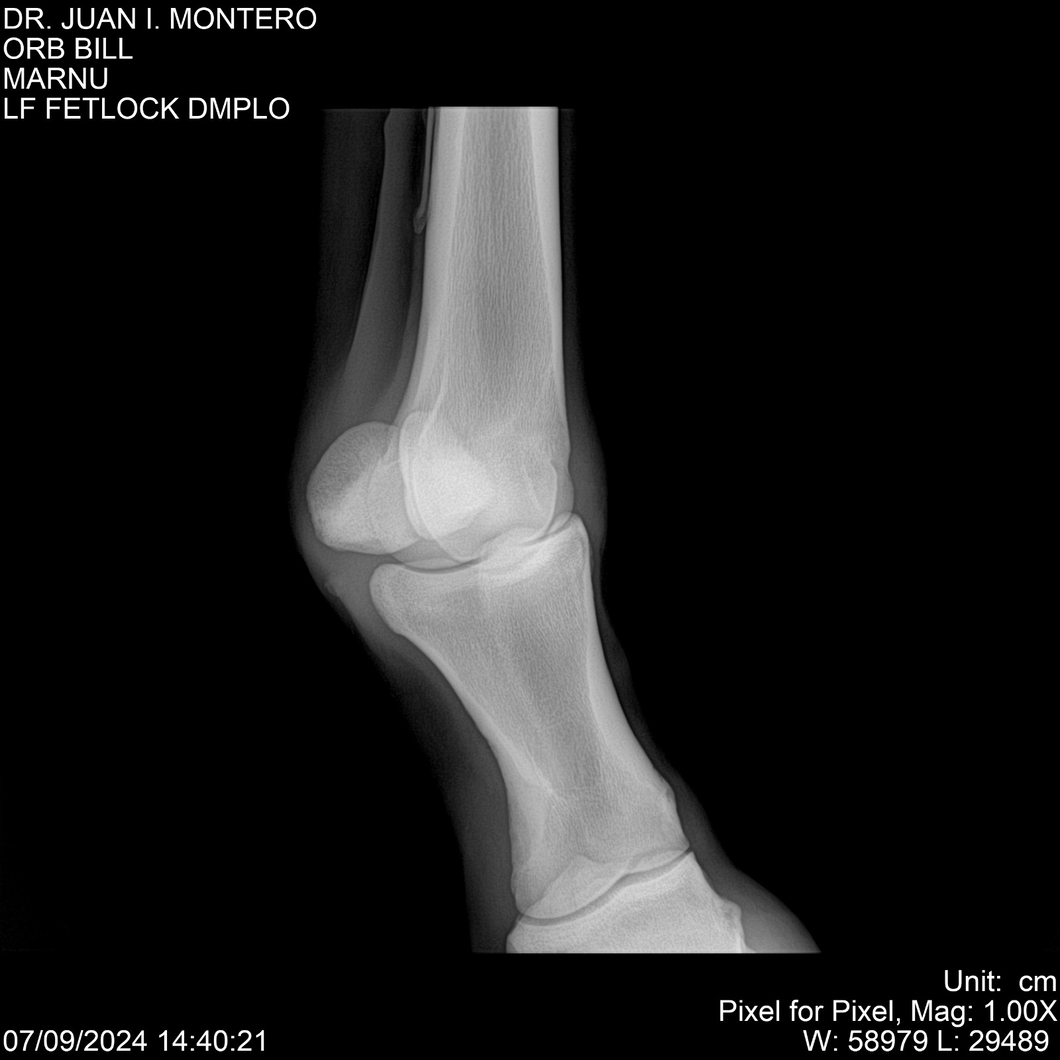

LOTE 7, ORB BILL 🔥 🔥 🔥 Lote Anterior Volver al remate Lote Siguiente Ficha Contacto Montevideo - Ficha del Lote Identificador: #282523 Categoría: Yeguarizos Montevideo - 83 Visualizaciones ClicData Contacto Empresa: Abelenda N. R., Walter Hugo Nombre*: Teléfono* : E-mail* : Mensaje Enviar Registrese gratis Este contenido Exclusivo está disponible sólo para usuarios registrados Ingresar